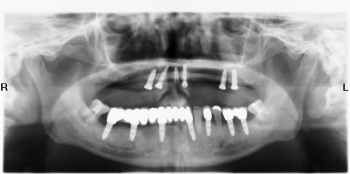

Hình trước và sau khi cấy implant

4. Cho phép chụp toàn bộ hàm răng và xương hàm, rất cần thiết trong chẩn đoán và điều trị nha khoa, đặc biệt trong cấy ghép implant, chỉnh hình răng, nhổ răng khôn, và những trường hợp phức tạp, cần có kế hoạch điều trị toàn diện.